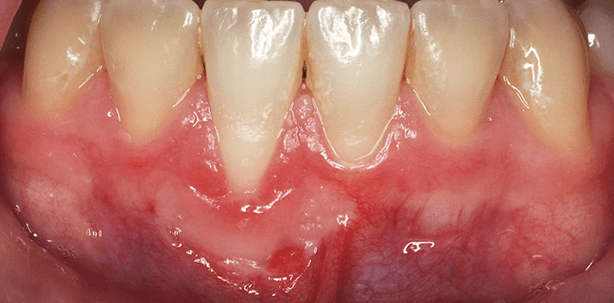

Beide Patientinnen waren zu Behandlungsbeginn 17 Jahre alt und hatten Beschwerden im Bereich 31 (Fall 1, Abb. 1) bzw. 41 (Fall 2, Abb. 2). Es zeigten sich jeweils Rezessionen (Miller-Klasse II) mit fehlender (Fall 1) bzw. sehr schmaler (Fall 2) keratinisierter Gingiva. In beiden Fällen waren diese Befunde isoliert an einem Zahn vorhanden. Beide Patientinnen waren Nichtraucherinnen. Es wurde eine zweizeitige Therapie vorgeschlagen. Zunächst ein freies Schleimhauttransplantat (FST) vom Gaumen zur Schaffung einer neuen Attached Gingiva. Anschließend, falls es erforderlich werden würde, sollte ein koronaler Verschiebelappen erfolgen. Dem Vorschlag wurde in beiden Fällen zugestimmt.